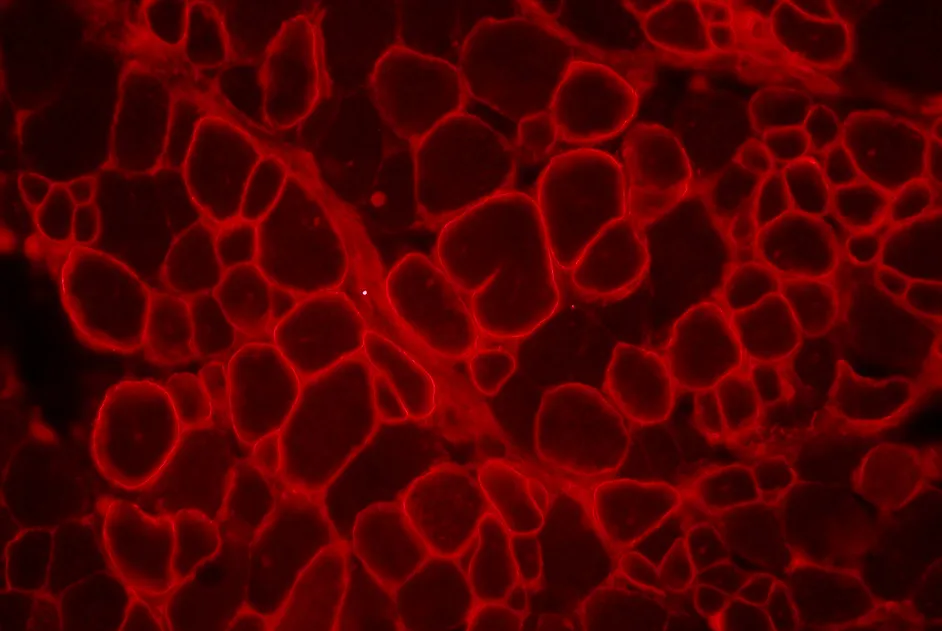

Une thérapie génique avec de nouveaux AAV-calpaïne 3 améliore les symptômes de souris modèles de LGMD2A sans être toxique pour leur cœur.

Un nouveau modèle de souris de la DMD a été développé pour étudier la transplantation de cellules souches musculaires à long terme.